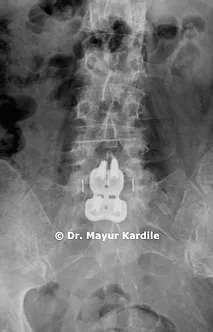

Anterior Lumbar Interbody Fusion (ALIF) for L5-S1 Recurrent Disc Herniation with Foraminal Stenosis

A 67-year-old lady suffered from severe left side leg pain. She had an L5-S1 discectomy 8 years back and was doing perfectly well after that. She started having leg pain for the past 6 months

MRI revealed recurrent disc herniation at L5-S1 with foraminal stenosis on left side

Anterior Lumbar Interbody Fusion (ALIF) surgery was done on her and she had a dramatic relief from leg pain.

ALIF provides indirect decompression of the spinal nerves and is an excellent technique to avoid nerve roots that are already scarred in case of revision spine surgery.

Also, it restores the normal lordotic angle of the lumbar motion segment